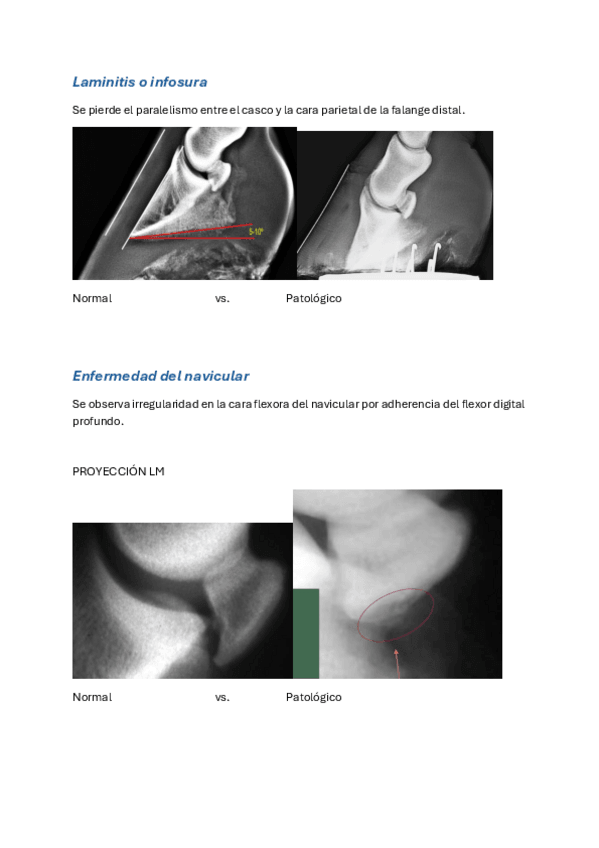

EQUINO

He publicado nuevos apuntes de 3º Diagnóstico Por la Imagen: EQUINO

ecografia-de-tendones.pdf

EQUINO-cabeza-columna-torax-abodmen.pdf